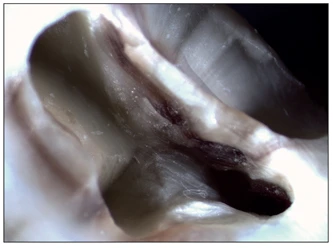

Hình 19-2 Hình ảnh phóng đại cho thấy lỗ mở tủy và rãnh tự nhiên ở một răng cối lớn thứ nhất hàm trên. Hình dạng của xoang mở tủy cho thấy sự cân bằng giữa khả năng quan sát và sự bảo tồn mô ngà lành mạnh.